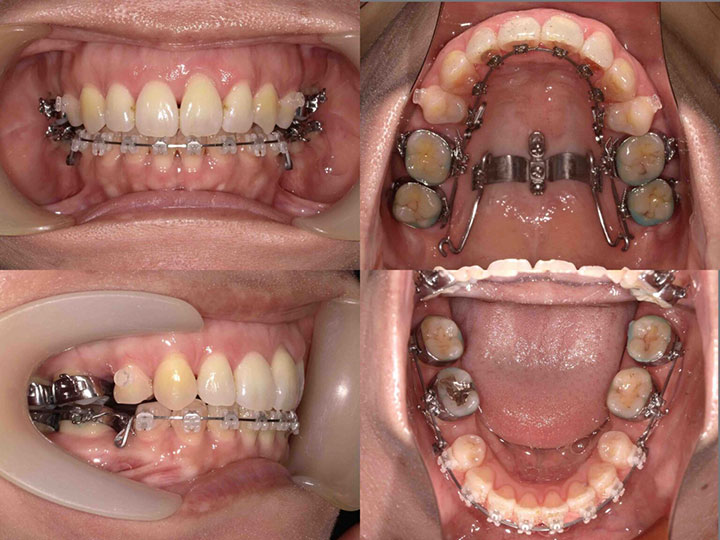

口の閉じ辛さの治療

治療期間:1年5ヶ月

上下顎4番を抜歯して、前歯を後方に移動しました。